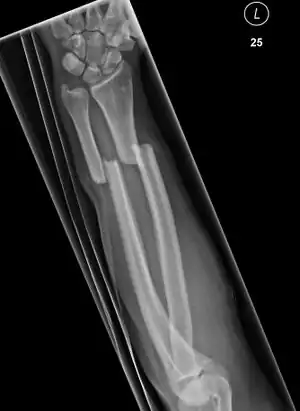

Front view of bowing fractured radius and ulna -

Side view of bowing fractured radius and ulna